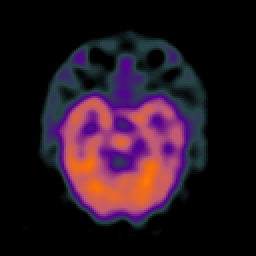

SPECT TC Study #1 -- Slice #19

[Home][Help][Clinical][Tour 1][Tour 2][Tour 3] Slice 19